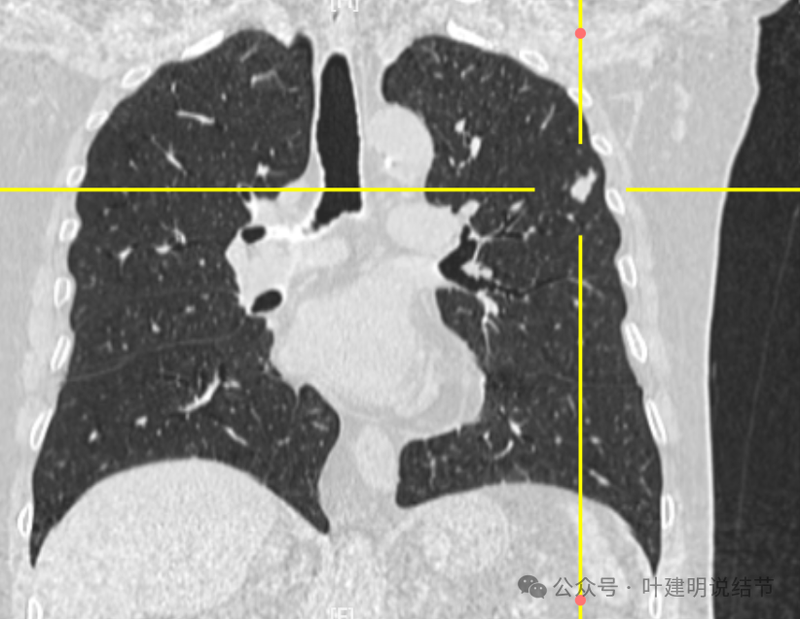

冠状位病灶形态稍不规则,实性密度,表面不平。

我想我们这样来考虑问题:1、左肺上叶主病灶实性密度、随访持续进展,边缘有血管穿过并形成血管弯征,这种病灶要警惕是恶性的;2、位置在胸膜比较近的地方,单孔胸腔镜下局部切除方便,即便真的是肉芽肿性炎或者良性,手术创伤以及切除的肺组织并不多,但是却可以去除病灶并明确诊断;你赌他是良性,但如果事实上是恶性,实性密度的随访会延误病情。而切除即便良性也是利大于弊;3、左肺上叶这个病灶本身没有结核的典型表现,整体轮廓比较清楚,没有卫星灶,也没有边缘偏模糊的情况,影像上并不是很考虑是结核或者是肉芽肿性炎。虽然肉芽肿性炎也确实有随访进展的,但我们要从风险高低的角度来考虑;4、右侧腔静脉旁以及龙头下都有肿大淋巴结,左侧主动脉弓下也有肿大淋巴结。当时左肺上叶病灶非常微小的时候,淋巴结肿大已经存在。而且对比淋巴结没有进一步增大,左侧这个病灶却持续进展。这用一元论不能够解释,如果淋巴结肿大是反应性增生或者肉芽肿性炎症,和左侧主病灶是肿瘤性质的,那么就非常能够解释这样的现象。所以你这个病灶我的意见是建议胸腔镜下微创切除。先做楔形切除,如果良性结束手术,如果恶性可以考虑淋巴结采样,但个人并不主张一定要肺叶切除。我的截图上面蓝色箭头标注的是纵隔肿大的淋巴结,红色框起来的是左肺上叶主病灶不同时间段的样子。意见供参考!